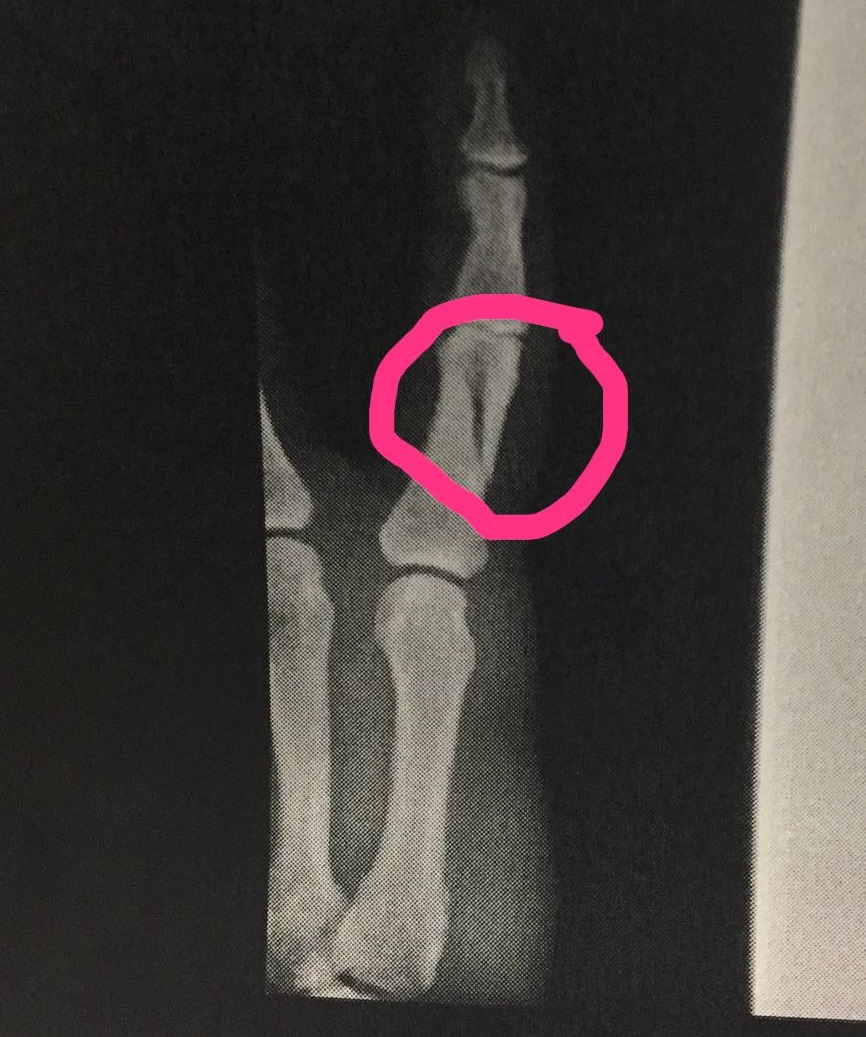

Ruyman no podrá estar bajo palos en la retaguardia de los del sur de Lanzarote. El cancerbero se fisuró una de las falanges de su mano que no le permitirá llegar en condiciones a la disputa choque. De hecho, no jugará en Haría pero tampoco lo hará, probablemente, en el próximo mes hasta recuperarse de este contratiempo que llega a pocas fechas de concluir el campeonato regular.